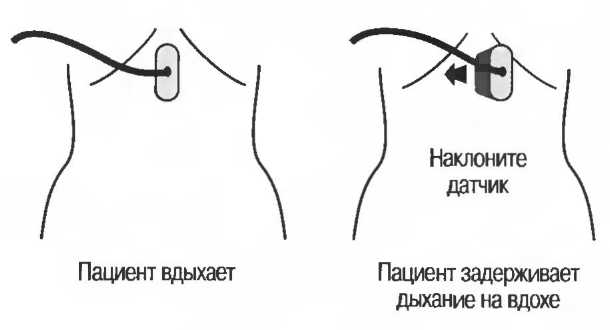

|

5. |

Поджелудочную железу. |

|

6. |

Почки. |

|

7. |